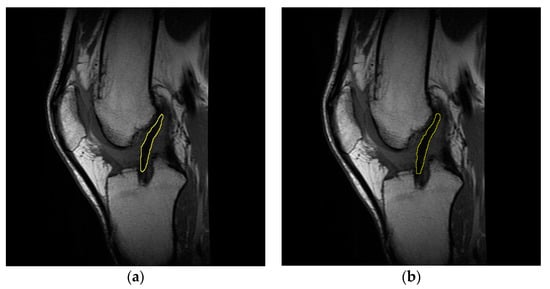

Concerning the evaluation of the T2 signal for the injured ligament, healthy ligament, and graft, the slice of each sagittal sequence showing the clearest image of Blumensaat’s line was selected [31,32]. From this perspective, the use of a single section to acquire the T2 signal allows for the exclusion of undesirable factors such as magnetization transfer and crosstalk; these issues might indeed occur if a multi-section acquisition is used [33,34]. After obtaining the T2 map by applying the Levenberg–Marquardt algorithm [35], the contours of the intra-articular portion of the graft/ACL were manually outlined on the mask obtained by overlaying the starting slice to the corresponding region in each T2 map image [36] (Figure 1). This procedure allowed us to evaluate the T2 signal of the purely tendinous/ligamentous portion, achieving substantial segregation from surrounding synovial tissue, which usually occurs throughout the course of graft maturation [37].

Representative sagittal images of the graft intra-articular portion, manually outlined on the starting slice (a) and on the mask obtained by overlaying the latter to the T2 map (b). Data concern subject #6 at four months follow-up.